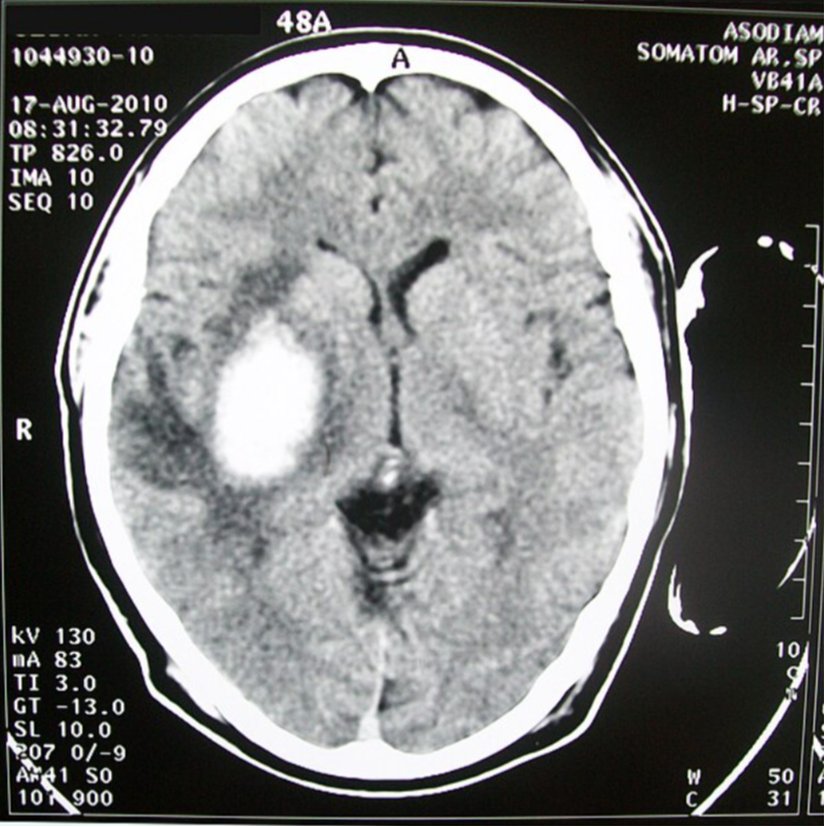

İntraserebral kanama, hayati tehlikesi bulunan tıbbi bir acil durumdur. Bu nedenle zamanında teşhis kritik öneme sahiptir. İntraserebral kanamayı iskemik inmeden güvenilir bir şekilde ayırmak için beyin görüntülemesi yapılmalıdır. Bilgisayarlı Tomografi (BT) ve Anjiyografi veya Magnet Rezonans Tomografi (MRT) ve Anjiyografi başlangıç için uygundur. Acil durumlarda Bilgisayarlı Tomografi, hız ve maliyet bakımından daha kullanışlı olup tanılama becerisi açısından ise Magnet Rezonans Tomografi ile anlamlı bir farkı bulunmamaktadır.

Beyin kanamaları için en büyük risklerden biri yüksek tansiyon hastalığıdır. Yüksek tansiyon zamanla beyin damarlarının iç çeperinin elastik yapısını zedeleyip en sonunda direncini kaybetmesine neden olmaktadır. Bu direnç kaybı da zedelenmenin olduğu damar bölgesinden kanamanın başlamasına yol açmaktadır. Bilgisayarlı Tomografi ile kanamanın tespiti sonrası bu kez kontrast madde ile beyin damarlarının görüntülenmesi, kanamanın kaynaklandığı damarların tespiti ve tedavi stratejisi açısından hekimlere bilgi vermektedir.

Tedavi yaklaşımları konservatif (koruyucu) ve cerrahi yöntemler olarak ikiye ayrılır. Beyin kanamasının Bilgisayarlı Tomografi'de tanılanması kanamanın zamansal boyunu göstermez. Kanamanın hâlâ devam edip etmediği, sızma şeklinde mi yoksa dramatik şekilde yoğun bir kanama mı olduğu bu görüntülemeyle anlaşılmaz ancak pratik olarak kanamanın devam ettiği varsayılarak bu durumu engelleyici hemostatik stratejiler ilk aşamada uygulanır.